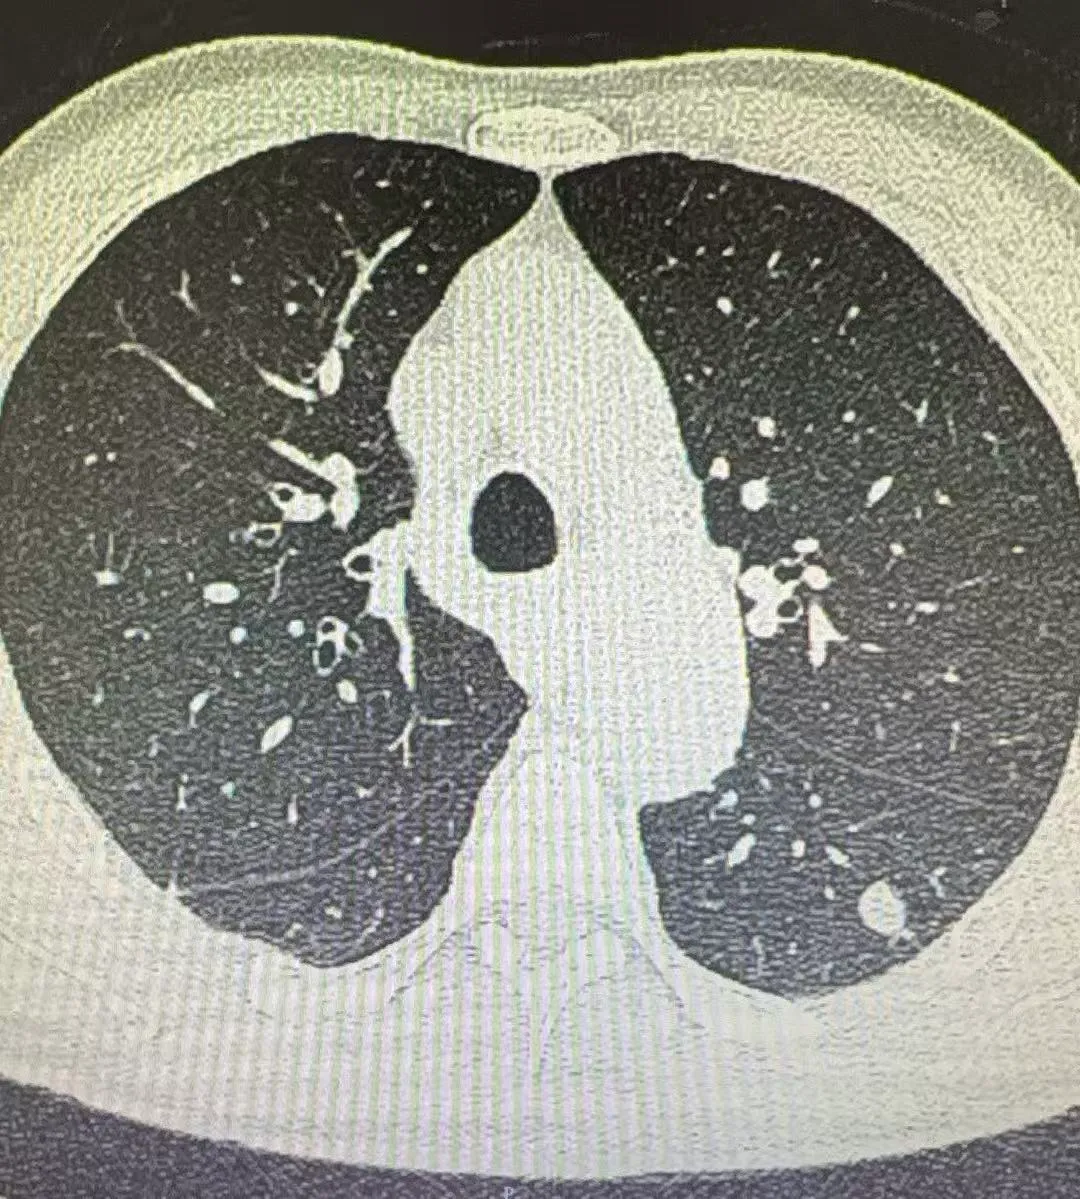

患者伦某,因胸闷、憋气1月就诊于我院老年医学科,行胸部CT检查示右肺上叶后端结节,考虑恶性可能性大,随转入我科。在拟上手术前一天,经张振江主任阅读病史及综合分析后考虑结节存在良性可能,果断终止手术,后行穿刺诊疗,确诊为良性结节。随访至今略有缩小。

2026.02.03 胸部CT